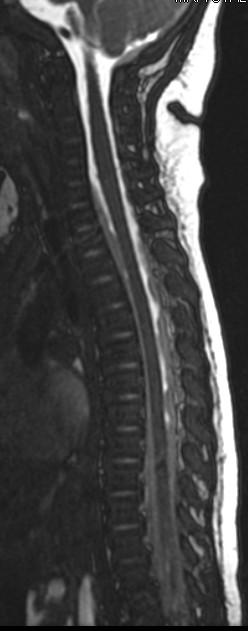

NAT: Spine MRI Cervical or Total, without contrast ½ to 2/3 of AHT have unsuspected spinal injury only .3-2.7% have bony abnormality on C spine

Brain swelling and herniation

Cord edema/ischemia Kadom et al, 2014, >75%

“Soft tissue or ligamentous injury” in the Cervical Spine

 Posterior soft tissue edema 50%

 Interspinous ligamentous edema/injury

 In cervical region, as high as 71% <1 year of age

Chaudhary, Kadom, Rabbitt 2019 Colombari, 2021

Spinal Injury patterns in AHT: SDH, compression fxs

[Choudharyetal,2014][Colombarietal,2021]

Nuchal ligament tear

Interspinous edema

Prevertebral fluid

Anterior vertebral body fracture T12 75% spine MRI: Extensive subdural/epidural hemorrhage, thecal sac tapering

Look for crowding and anterior displacement of the nerve roots